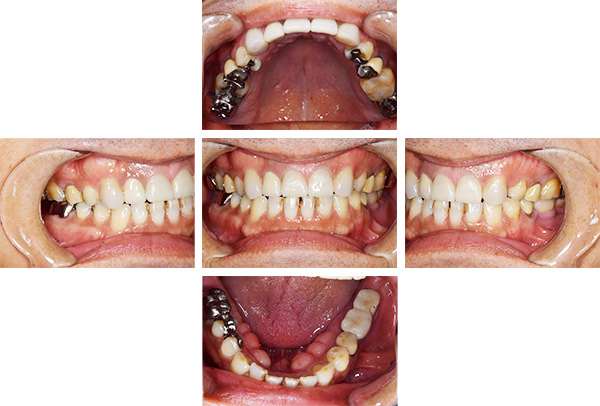

症例写真(治療前)

担当医師所見

治療前:

八重歯が目立ちます。また銀歯もおおく、見た目が気になります。虫歯も散見できます。

レントゲン写真(治療前)

根の治療を3本すでに治療されています。1本根の奥の詰め物が疎になっていますので、根の部分の再治療も行う必要がありそうです。銀歯の中で虫歯になっているものもあります。